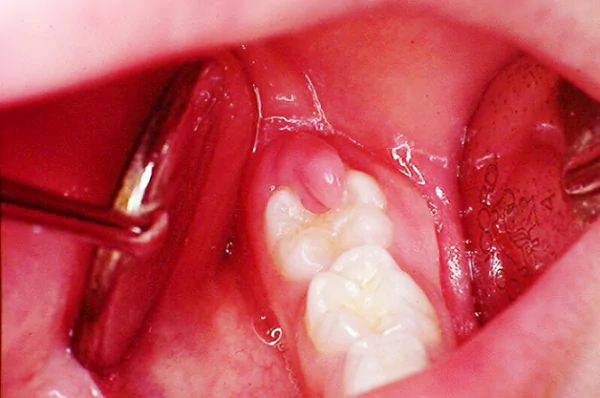

Viêm lợi trùm (Pericoronitis) là một trạng thái bệnh lý nhiễm trùng khu trú tại tổ chức mô mềm bao quanh thân răng đang trong quá trình mọc, phổ biến nhất là răng khôn (răng số 8). Tình trạng này phát sinh do sự hình thành một vạt nướu che phủ một phần bề mặt răng, tạo ra một khoang trống sinh học tạo điều kiện cho vi khuẩn kỵ khí và mảng bám thức ăn tích tụ. Nếu không được chẩn đoán và xử lý bằng các phác đồ y khoa chuyên sâu, viêm lợi trùm có thể dẫn đến các biến chứng lan tỏa sang vùng hàm mặt và ảnh hưởng đến sức khỏe hệ thống. Bài viết sau đây cung cấp thông tin chuyên môn về cơ chế bệnh lý, các giai đoạn tiến triển và giải pháp can thiệp hiện đại tại hệ thống Nha khoa Xanh Dental.

Viêm lợi trùm được xác định là phản ứng viêm nhiễm của mô nướu đối với các tác nhân vi khuẩn tại vị trí răng mọc dở dang. Căn cứ vào biểu hiện lâm sàng, bệnh lý này được phân chia thành hai thể chính:

Sự hình thành túi nướu bệnh lý: Khi răng khôn mọc lệch hoặc mọc kẹt, một phần niêm mạc nướu không thể tiêu biến mà bao phủ lên thân răng. Khoảng trống giữa mặt nhai của răng và vạt nướu này trở thành môi trường yếm khí lý tưởng cho vi khuẩn Streptococcus và Bacteroides phát triển.